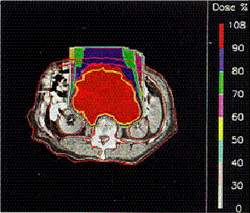

| Облучение g-квантами | Облучение протонами |

| Вид лучевой терапии |

Локализация дозы | Лечению поддаются | |

|---|---|---|---|

| резистентные опухоли | |||

| g от 60Co | плохая | + | - |

| g от e Ee≈20 МЭв + IMRT |

хорошая | + | - |

| протоны | отличная | + | - |

| нейтроны | плохая | + | + |

| ядра 12C | отличная | + | + |